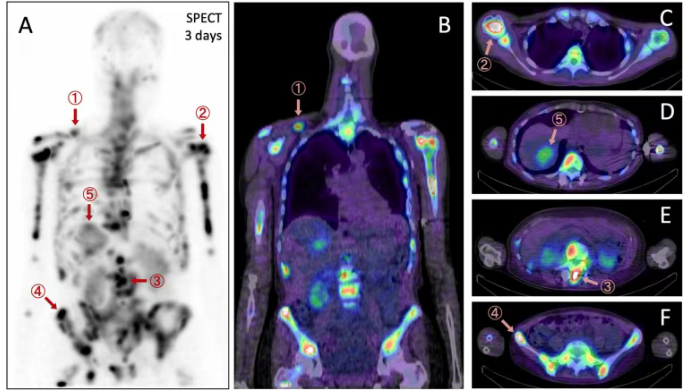

该名对多线治疗耐药的患者在接受7.124 GBq的单次给药后,经单光子发射计算机断层扫描/计算机断层扫描(SPECT/CT)及平面显像证实,药物在骨、肝及淋巴结等多处转移灶中具有特异性摄取。初步剂量学评估显示,部分骨转移灶吸收剂量达到45.8 Gy,中位肿瘤剂量为3.1 Gy/GBq,而肾脏平均剂量为0.66 Gy/GBq,安全可管理。短期随访显示患者耐受良好,病情趋于稳定。